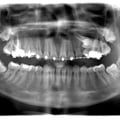

Руйнування зубів - результат тривалого користування бюгельними знімними протезами